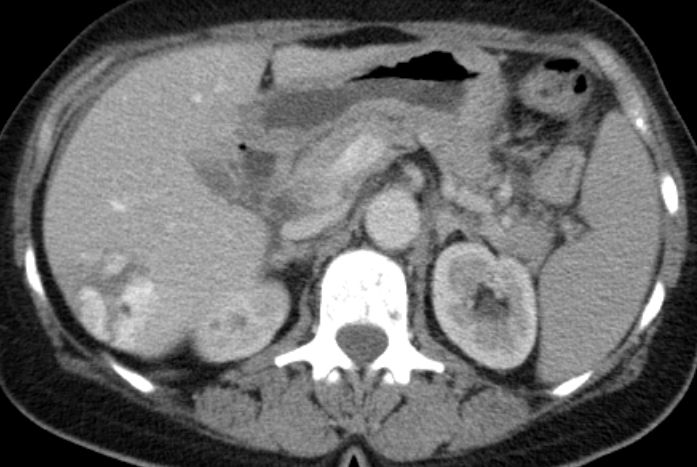

Colon 74-jähriger Mann mit Ileus durch einen Tumor im Colon ascendens.

Histologie: gut differenzierter neuroendokriner Tumor, G1, Ki67 unter 1%.